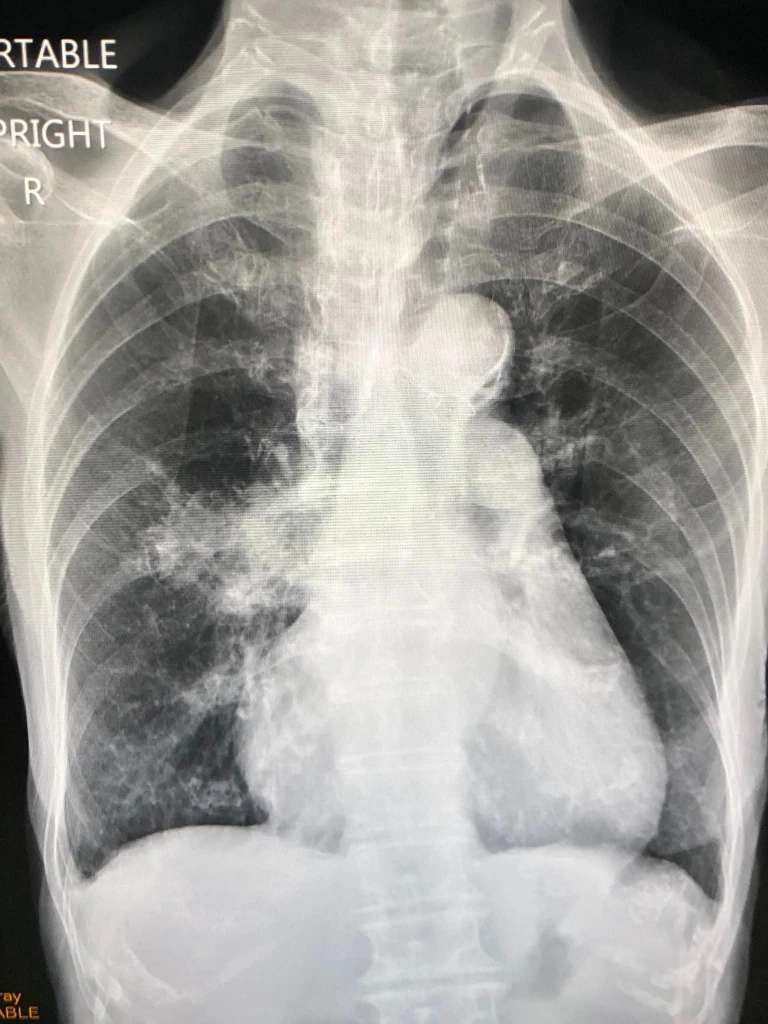

ผู้ป่วยหญิงไทยอายุ 85 ปี ได้รับวัคซีนแอสตร้าเซนเนก้า 2 เข็ม มิย. 64 และ กย. 64 กระตุ้นเข็ม 3 ด้วยวัคซีนโมเดอร์นา 19 ม.ค. 65 เริ่มมีไข้ต่ำๆ ไอ เสมหะสีขาว มีน้ำมูกเล็กน้อย 3 วันก่อนมารพ.ไม่เจ็บคอ ไม่เหนื่อย จมูกได้กลิ่น ลิ้นได้รส ไม่ท้องเสีย มีโรคประจำตัวหอบหืด ต้องใช้ยาพ่นขยายหลอดลมที่บ้าน และมีโรคหัวใจ เคยผ่าตัดหัวใจมาก่อน ลูกชายเพิ่งติดเชื้อไวรัสโควิดก่อนหน้านี้ไม่กี่วัน ตรวจร่างกาย ฟังเสียงปอดปกติ วัดระดับออกซิเจนที่ปลายนิ้วปกติ เอกซเรย์หัวใจโต แต่ปอดปกติ ตรวจ RT-PCR SARS-CoV2 เมื่อวันที่ 23 กุมภาพันธ์ 65 ให้ผลบวก ถึงแม้ผู้ป่วยรายนี้มีอาการน้อย แต่มีความเสี่ยงเนื่องจากอายุมาก มีโรคหอบหืด โรคหัวใจ จึงให้เข้านอนสังเกตอาการในโรงพยาบาล

ระหว่างอยู่รพ.ผู้ป่วยไม่มีไข้ ไอเล็กน้อย ไม่เหนื่อย วัดระดับออกซิเจนปกติ ไม่ได้ให้ ยาฟาวิพิราเวียร์ ให้ยาแก้ไอ รักษาตามอาการ และให้ยาประจำตัวของผู้ป่วย ผู้ป่วยดีขึ้นต่อเนื่อง เอกซเรย์ปอดซ้ำ 1 สัปดาห์ต่อมา ปอดปกติ ให้กลับบ้านได้ (ดูรูป)